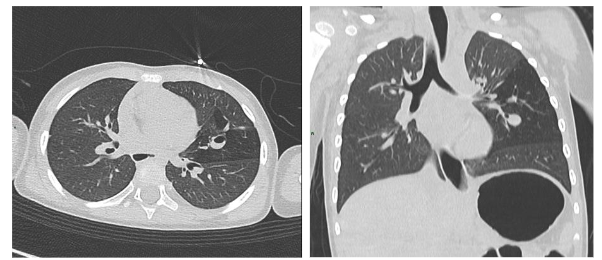

In the postnatal period, the gold standard remains contrast-enhanced computed tomography (CT angiography), which enables high-resolution evaluation of the bronchial tree integrity, characterization of parenchymal architecture (Figure 4), and assessment of the number and size of cysts (Figure 2). It also allows for precise visualization of aberrant systemic vessels (Figure 5), as well as evaluating compressive effects on mediastinal structures.

Postnatal magnetic resonance imaging (MRI) has gained ground as a radiation-free alternative, particularly relevant in infants and for long-term follow-up. High-resolution MRI can allow postponement of CT angiography in asymptomatic neonates until surgery, thereby avoiding early exposure to ionizing radiation. The introduction of ultrashort echo time (UTE) and zero echo time (ZTE) sequences has overcome traditional limitations of thoracic MRI by allowing visualization of aerated lung parenchyma. Furthermore, dynamic MRI sequences have opened a new dimension in functional assessment by enabling ventilation and perfusion studies, which are particularly useful when functional impairment exceeds what is suggested by structural findings.